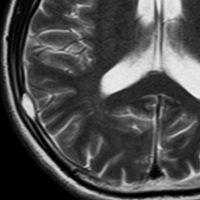

51歳の男性にみられたものです。脳ドックをきっかけにみつかりました。何もないところから発生して増大してまた3ヶ月くらいで消失していきます。左上から1月間隔くらいのMRIです。

もちろん生検手術などしません。

ガドリニウム像です。極期を過ぎているのでリング状増強で,これも縮小消失していきます。